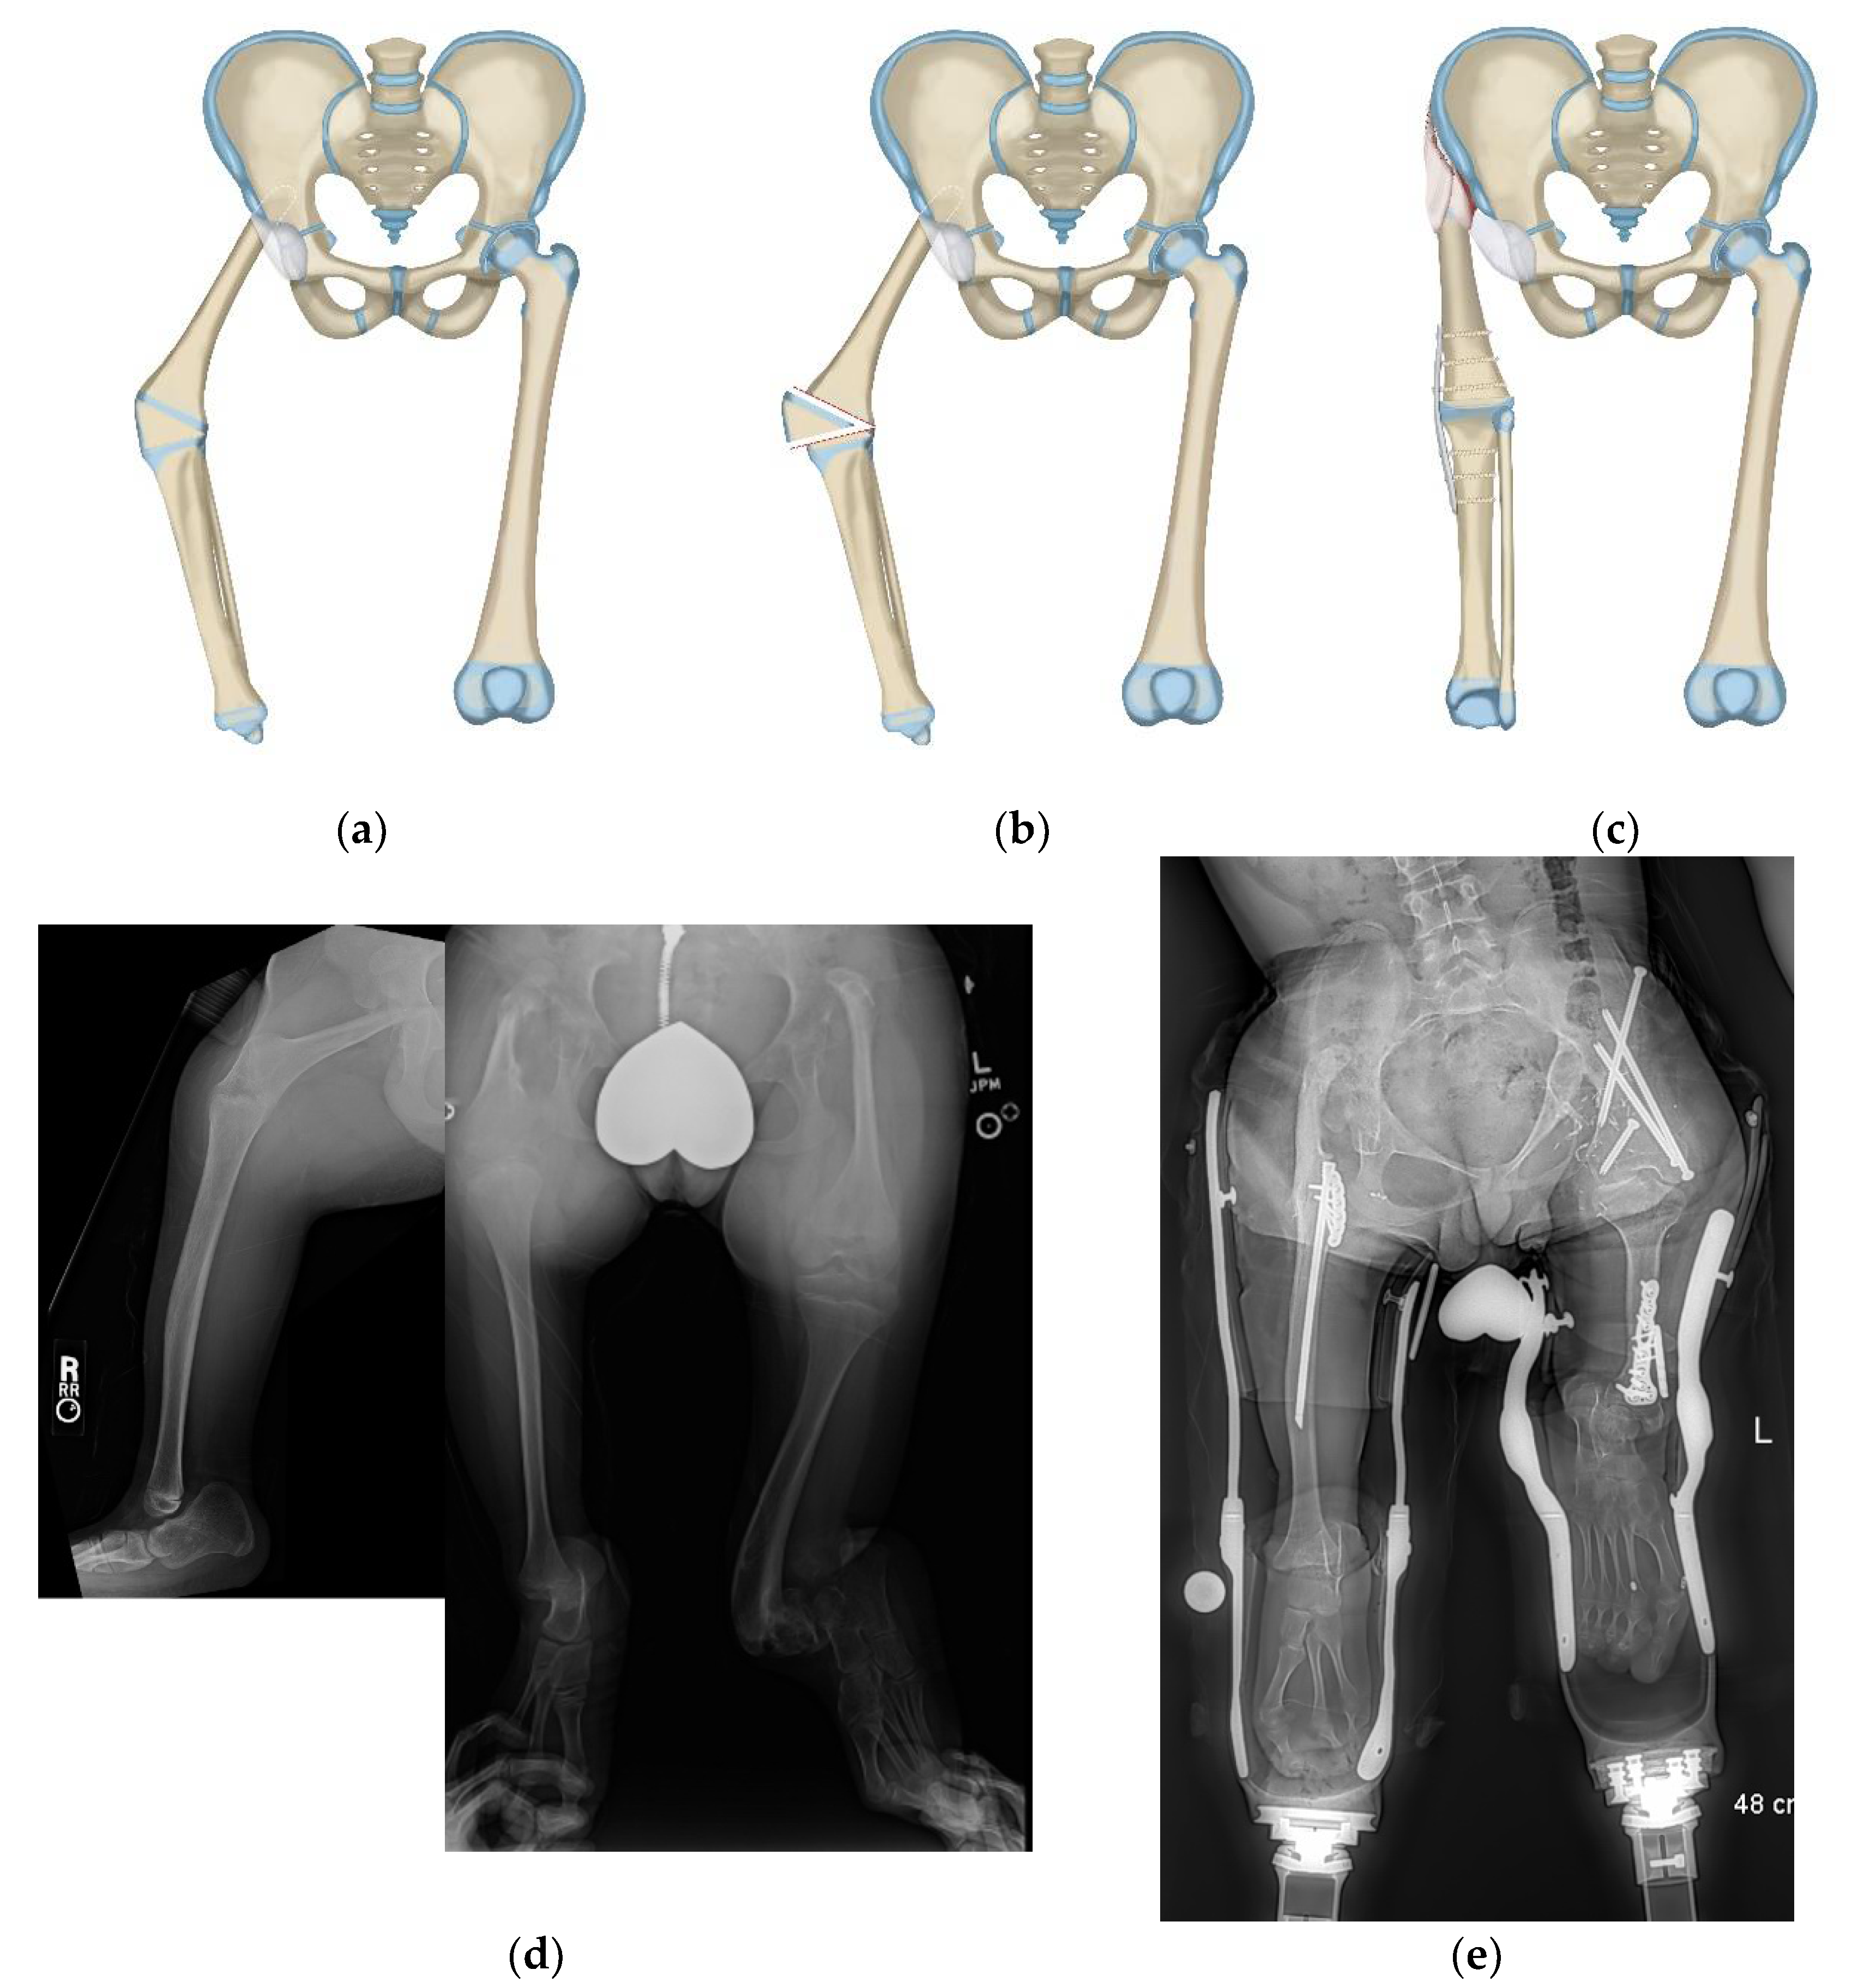

Figure 2.

(a) Illustration of CFD Paley type 3 (a or b), (b) Illustration after Brown rotationplasty for Paley type 3 (a or b), (c) AP pelvis x-ray of 14-year-old boy with Paley type 3b CFD, (d) Preop standing erect leg x-ray of same boy, showing that the ankle is at the level of the opposite knee (incidentally this patient also has multiple osteochondromas), (e) AP pelvis radiograph in same boy, 7 years after healed Brown rotationplasty, (f) Sanding radiograph with prosthetic 7 years after Brown rotationplasty with supramalleolar osteotomy for ankle realignment. Clinically he has excellent gait and function.

Figure 3.

(a) Paley–Brown Rotationplasty illustration for Paley type 3 (a or b), (b) AP pelvis radiograph in 3-year-old girl with Paley type 3a CFD, (c) Standing long radiograph showing the left ankle is at the level of the right knee, (d) Standing long radiograph two years after Paley–Brown rotationplasty. The ankle is at the level of the opposite distal femoral physis (level of knee center of rotation). Clinically she has excellent gait and function.

Figure 6.

(a) Illustration of CFD type 1a3 or 1b. (b) Illustration showing the first step which is SUPERhip procedure with resection of knee joint. (c) Illustration showing the second step which is PaleySUPERhip–Van Nes rotationplasty at level of the knee fusion. (d) AP pelvis on 36-year-old man with CFD type 1b with prior failed hip surgery. (e) Standing radiograph in same man showing ankle at level of opposite knee joint. (f) Long lateral and AP radiographs showing the knee joint in the same patient was unstable, deformed and subluxated. (g) Standing radiograph one year after PaleySUPERhip–Van Nes procedure including SUPERhip, knee fusion and supramalleolar osteotomy, wearing rotationplasty prosthetic. Ankle is at level of opposite knee. This procedure greatly improved his quality and of life, gait and function.

Figure 7.

(a) Illustration of CFD type 2c with congenital knee fusion with knee flexion deformity. The fibrous femoral neck anlage tethers the upper femur from migrating proximally. (b) Illustration showing the first step which is correction of knee flexion deformity with excision of distal femoral physis. (c) Illustration of the second step which is PaleySling–Van Nes rotationplasty. The rotationplasty is performed through the knee fusion site. The proximal femur is stabilized using the fascia lata by creating a sling around the proximal femur. The sling plus the fibrous neck anlage stabilize the upper femur from migrating proximally and while preserving the hip flexion-extension mobility (d) AP long radiograph (right) of a 14-year-old boy with bilateral CFD. The right side is classified as type 2c and also has a congenital knee fusion as seen on the long lateral radiograph (left). On the left side it is classified as a CFD type 3b and the knee joint is present and functional. (e) Standing long radiograph one year after bilateral rotationplasty performed in two separate surgeries. On the right side the rotationplasty was performed through the congenital knee fusion site together with a sling procedure at the hip (PaleySling–Van Nes). On the left side a Paley–Brown rotationplasty was performed together with a supramalleolar osteotomy for realignment.